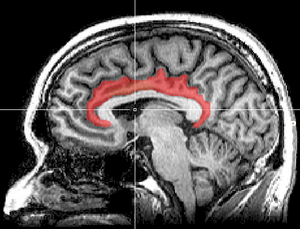

القشرة الحزامية cingulate cortex، تعرف أيضاً بالقشرة الحوفية، هي جزء من المخ يقع في الجانب الإنسي من القشرة المخية. القشرة الحزامية تشمل التلفيف الحزامي بأكمله، والذي يقع فوق الجسم السفني مباشرة، ويستمر حتى التلم الحزامي. القشرة الحزامية عادة ما تعتبر جزءاً من الفص الحوفي.

تستقبل القشرة المخية الإشارات العصبية من المهاد والقشرة الجديدة، وترسلها إلى القشرة الشمية الداخلية عن طريق الحزام. وهي تعتبر جزءاً مدمجاً في الجهاز الحوفي، المسئول عن تشكيل ومعالجة المشاعر،[1] التعلم،[2] والذاكرة.[3][4] الجمع بين هذه الوظائف الثلاثة يجعل للقشرة الحزامية تأثير كبير في ربط المخرجات السلوكية بالمشاعر (على سبيل المثال، إجراء ما يتطلب استجابة عاطفية إيجابية، والذي يظهر أثره في التعلم).[5] هذا الدور يجعل القشرة الحزامية بالغة الأهمية في بعض الاضطرابات مثل الإكتئاب[6] وإنفصام الشخصية.[7] ويلعب أيضاً دوراً في الوظائف التنفيذية والتحكم في التنفس.